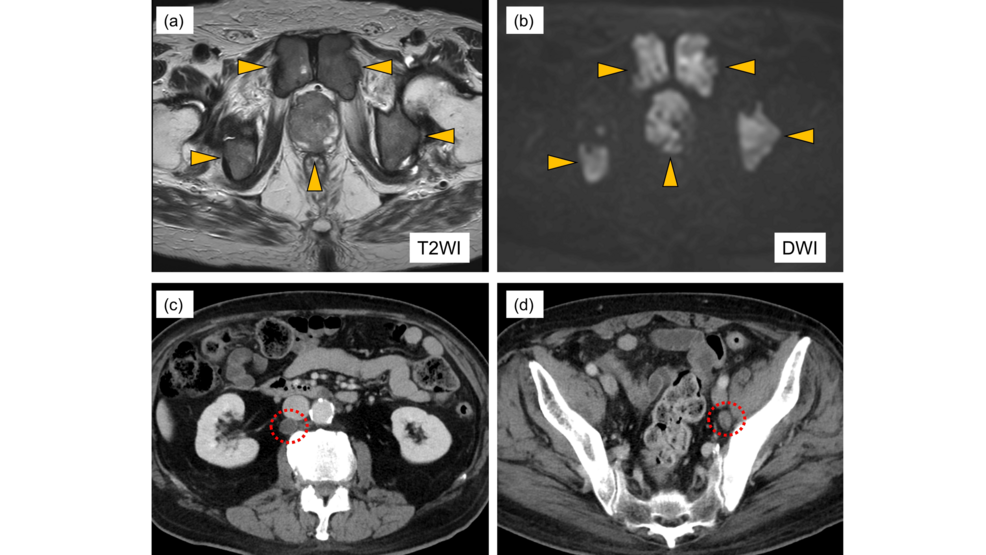

El antígeno prostático específico (PSA) es fundamental en la detección del cáncer de próstata (CP); sin embargo, los niveles de PSA en suero pueden permanecer engañosamente bajos en…